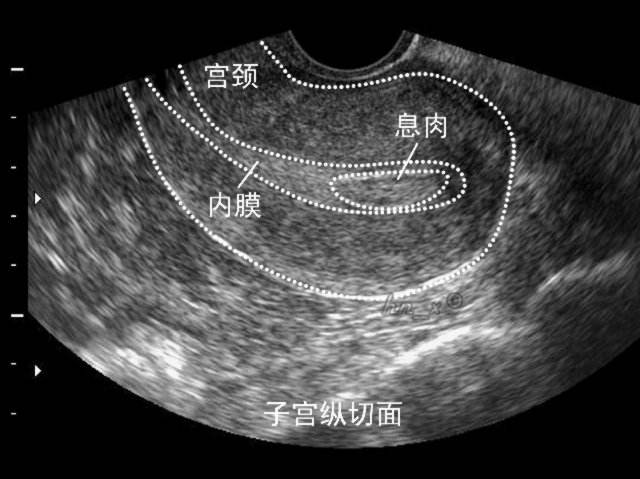

如果这时候测的内膜7-8mm甚至更厚,也不要着急。要是平时经期7天之内就干净,也没有不规则的阴道流血。应该也没有啥问题,最多可能存在小的内膜息肉。

因为内膜息肉需要通过B超才能检测,但是在小的时候,息肉在B超下可能只表现为内膜增厚。根据子宫内膜息肉的诊治规范,小于15mm的息肉,没有不正常阴道流血,没有不孕,可以2-3月后复查,还是在月经来的第5-6天做B超。没有明显变化就好。